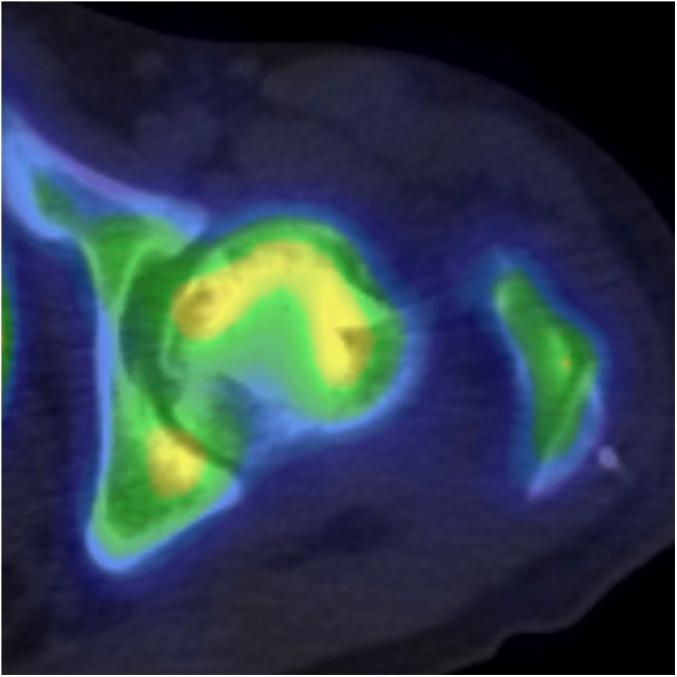

We retrospectively reviewed 28 consecutive patients who underwent anterior rotational osteotomy for the treatment of unilateral SIF (7 patients) or unilateral ON (21 patients). The mean duration of follow-up was 3.7 years (range, 2.0 to 6.2 years). Clinical and radiographic assessments were performed with use of the Harris hip score (HHS), sequential radiographs, and single-photon emission computed tomography/computed tomography (SPECT/CT) with Tc-hydroxymethylene diphosphonate performed 5 weeks after surgery.

The mean HHS (and standard deviation) in the SIF group improved significantly from 51.6 ± 11.7 preoperatively to 91.9 ± 7.1 at 1 year after surgery and to 96.9 ± 3.8 at the time of the latest follow-up (p = 0.0010 and 0.0002, respectively). Similarly, the mean HHS in the ON group improved significantly from 52.4 ± 13.7 preoperatively to 80.7 ± 10.0 at 1 year after surgery and to 88.2 ± 12.6 at the time of the latest follow-up (p < 0.0001 for both). The HHS was significantly higher in the SIF group than in the ON group at 1 year after surgery (p = 0.019), but there was no significant difference between the groups at the time of the latest follow-up (p = 0.10). A postoperative intact ratio (calculated as the intact area of the femoral head divided by the weight-bearing area of the acetabulum on an anteroposterior radiograph) of >80% was achieved in association with smaller femoral neck-shaft varus angles in the SIF group (10.0° ± 4.2°) as compared with the ON group (15.3° ± 8.2°). Postoperative progression of collapse at the anteriorly rotated subchondral lesion was observed in 5 patients (23.8%) in the ON group but no patients in the SIF group. SPECT/CT images showed that rate of increased tracer uptake at the collapsed lesions in the SIF group was significantly higher than that in the ON group (p < 0.0001).

SIF组的平均HHS(及标准差)从术前的51.6±11.7显著提高到术后1年的91.9±7.1,以及最近一次随访时的96.9±3.8(p分别为0.0010和0.0002)。同样,ON组的平均HHS从术前的52.4±13.7显著提高到术后1年的80.7±10.0,以及最近一次随访时的88.2±12.6(两者p均<0.0001)。术后1年时,SIF组的HHS显著高于ON组(p = 0.019),但在最近一次随访时两组之间无显著差异(p = 0.10)。与ON组(15.3°±8.2°)相比,SIF组获得了>80%的术后完整率(计算方法为股骨头完整面积除以前后位X线片上髋臼的负重面积),且股骨颈干角较小(10.0°±4.2°)。ON组有5例患者(23.8%)观察到前旋转软骨下病变处塌陷的术后进展,而SIF组无患者出现。SPECT/CT图像显示,SIF组塌陷病变处示踪剂摄取增加率显著高于ON组(p < 0.0001)。